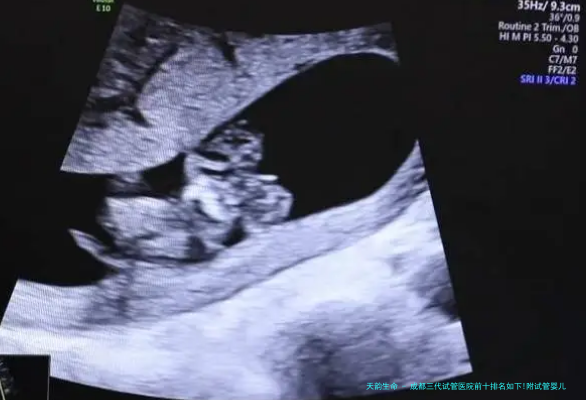

在成都这座医疗资源充裕的城市,试管婴儿技术已成为诸多家庭完成生育愿望的重要门路。其中第三代试管婴儿技术仰仗其基因检查筛选优势,为更多家庭带来了健康生育的希望。

这一项技术能够在胚胎移植前进行遗传学分析,筛选优质胚胎,明显提高妊娠成功率,并减低遗传病症风险。本文将根据2026年最新数据,介绍成都地域三代试管婴儿医院的选择指南及相关费用情况。

成都三代试管医院前十排名如下!附试管婴儿费用